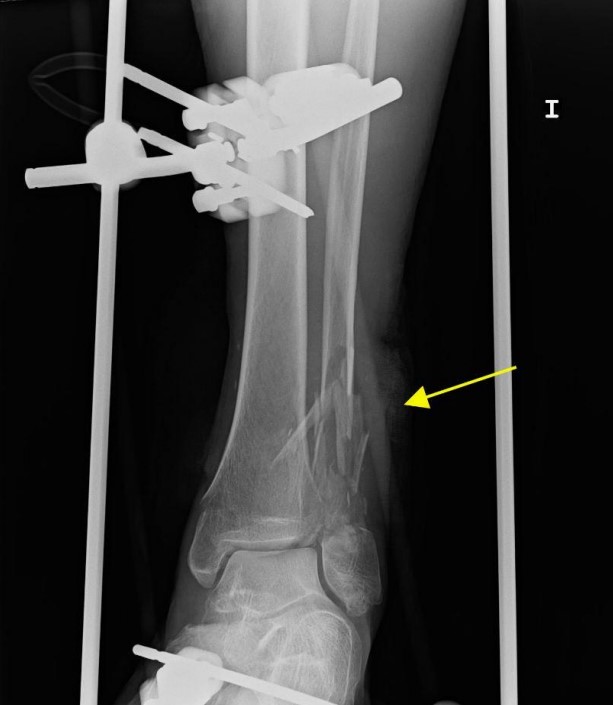

患者左下肢X線片顯示腓骨和脛骨骨折。胸片顯示上肺葉雙側肺泡混濁,這些不明確的斑片狀氣腔模糊是非特異性的,可見于肺水腫、誤吸或感染。繼續(xù)為患者行胸部CT檢查,CT顯示肺動脈干、左或右肺動脈主干或肺葉動脈無充盈缺損,雙側胸腔積液。肺窗顯示雙側上、左中肺野斑片狀磨玻璃影伴小葉間隔增厚。

圖1 左下肢X片。外固定器處理腓骨和脛骨骨折移位(黃色箭頭)